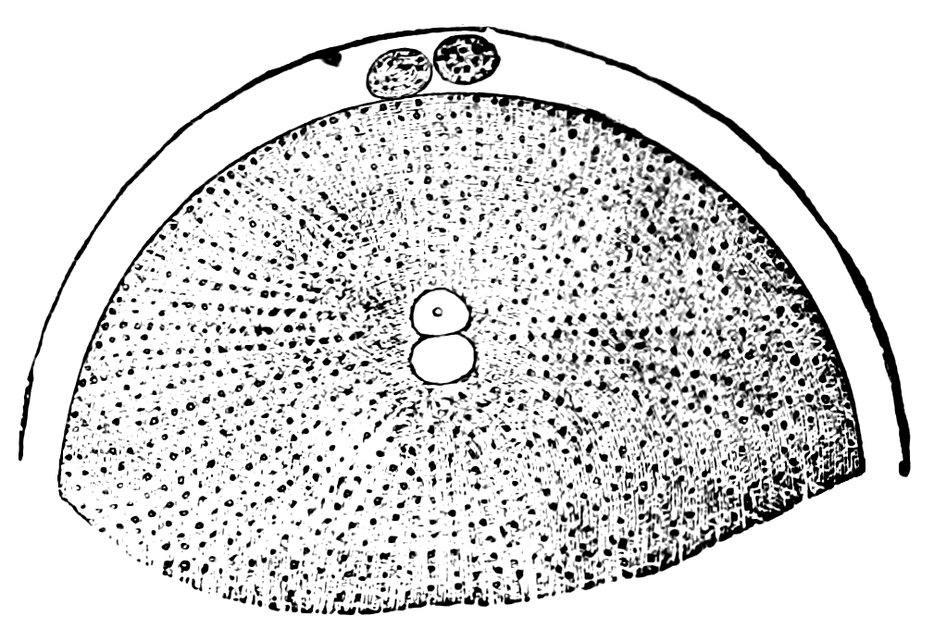

| 15. | Primitive follicles | 58 |

| 16. | Ripening follicles | 61 |

| 17. | Graafian follicles | 62 |

We must first consider the changes in the ovaries, which play an etiologically important part. At the onset of puberty, the follicular masses of the ovary exhibit a more active growth, the follicles increase in size, with their contained ova they approach the surface, and finally, by the bursting of the follicles, the ova are extruded. Then, in the life-phase in which conception occurs, and under the influence of the hyperæmia of all the pelvic viscera that accompanies this process, a notable development of the corpus luteum takes place, this latter body reaching its maximum size in the eleventh week of pregnancy, subsequently undergoing involution and leading to the formation of a considerable scar. Finally, in the critical period of life in which the menstrual flow ceases, a continually increasing growth and new formation of connective tissue-stroma takes place in the ovaries at the expense of their cellular constituents, and a regressive metamorphosis of the graafian follicles occurs.